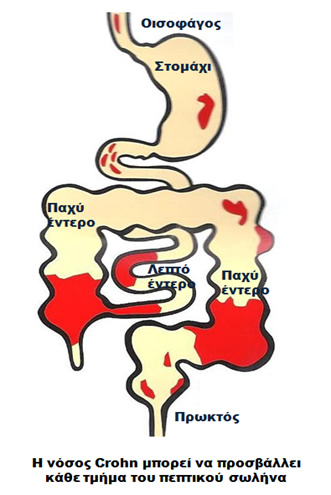

Η νόσος Crohn είναι μια χρόνια φλεγμονώδης νόσος αγνώστου αιτιoλογίας που μπορεί να προσβάλλει οποιοδήποτε σημείο του γαστρεντερικού σωλήνα. Μπορεί, ωστόσο, να προσβάλλει και άλλα όργανα του σώματος, όμως η συνηθέστερη θέση εμφάνισής της είναι ο πεπτικός σωλήνας.

Η νόσος Crohn περιγράφηκε για πρώτη φορά το 1932 από τον Burrill Β. Crohn και τους συνεργάτες του στο Νοσοκομείο Mount Sinai της Νέας Υόρκης. Οι ασθενείς με νόσο Crohn έχουν μία εφόρου ζωής φλεγμονή του γαστρεντερικού σωλήνα, η οποία ξεκινά από την εσωτερική επένδυση του τοιχώματος του, που είναι γνωστή ως βλεννογόνος, και, συνήθως επεκτείνεται και στα βαθύτερα στρώματα του. Η περιοχή στην οποία πιο συχνά αναπτύσσεται η φλεγμονή είναι το σημείο της ένωσης του λεπτού με το παχύ έντερο, δηλαδή εκεί που ο τελικός ειλεός, το τελευταίο τμήμα του λεπτού εντέρου, ενώνεται με το πρώτο τμήμα του παχέος εντέρου, που ονομάζεται τυφλό.

Ωστόσο, η νόσος Crohn μπορεί να εμφανισθεί σε οποιοδήποτε σημείο της εντερικής οδού, δηλαδή από τη στοματική κοιλότητα έως τον πρωκτό και μπορεί να επηρεάσει μία ή και περισσότερες περιοχές. Δεν υπάρχει τρόπος να προβλέψουμε ποιος και πότε θα αναπτύξει τη νόσο Crohn. Πρόκειται για μία χρόνια νόσο που μπορεί να εμφανισθεί ανά πάσα στιγμή, μπορεί να υφεθεί χωρίς εξήγηση και μπορεί να ξαναπαρουσιασθεί έντονα χωρίς προφανή αιτία.